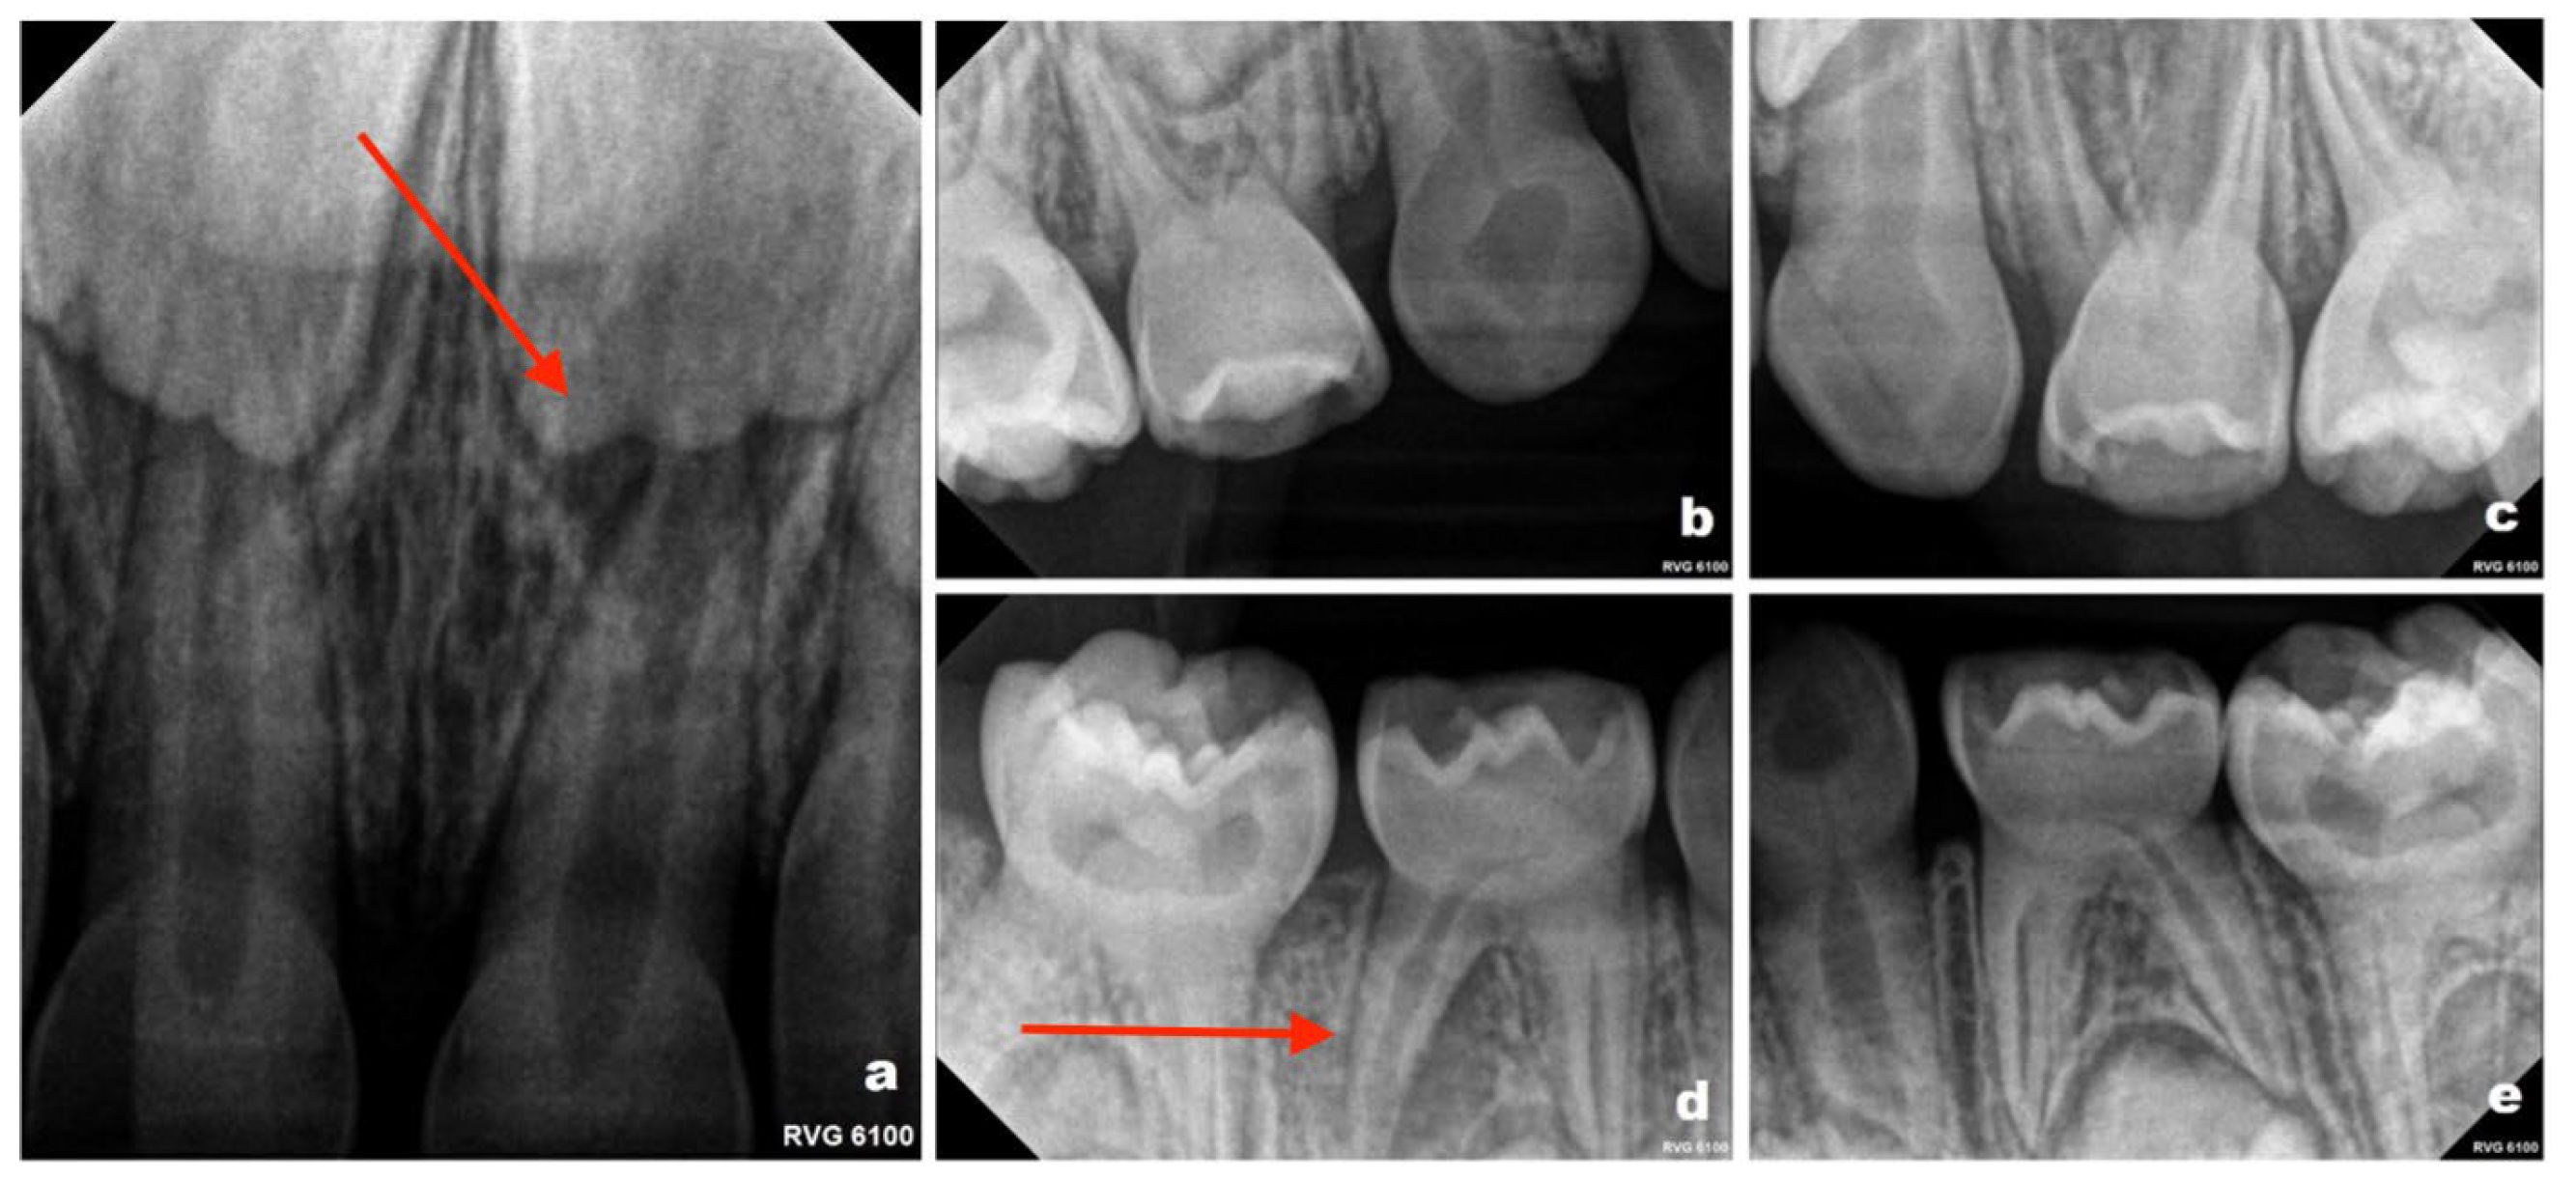

Tooth numbering in this report follows the Fédération Dentaire Internationale (FDI) two-digit notation system. Periapical radiographic evaluation (Figure 2a–e) revealed periapical changes associated with teeth 61 and 84. All first primary molars demonstrated obliteration of the pulp chambers and root canals, a radiographic feature consistent with DI. Teeth 53 and 73 exhibited marked narrowing of the pulp space in the cervical region. Tooth 83 could not be fully evaluated because it was not included within the radiographic field. Panoramic radiography was not performed during the course of treatment. Imaging was limited to periapical radiographs, which were considered sufficient for localized assessment of the affected teeth. Given the patient’s young age and variable cooperation, as well as the aim to minimize radiation exposure, more extensive imaging was not routinely indicated at that stage. Evaluation of the developing permanent dentition was therefore not performed radiographically during the early follow-up period. Radiographic monitoring was planned at approximately 6-month intervals, based on the patient’s high caries risk and susceptibility to dental pathology; however, the timing of imaging was also adjusted according to the child’s level of cooperation and clinical circumstances at each visit.

Figure 2. Periapical radiographs obtained in September 2022 (patient aged 3 years): (a) maxillary anterior region showing a periapical radiolucency associated with tooth 61 (Please note the area indicated by the red arrow in the figure); (b) upper right quadrant; (c) upper left quadrant; (d) lower right quadrant, demonstrating periapical changes at the distal root of tooth 84 (Please note the area indicated by the red arrow in the figure); (e) lower left quadrant.